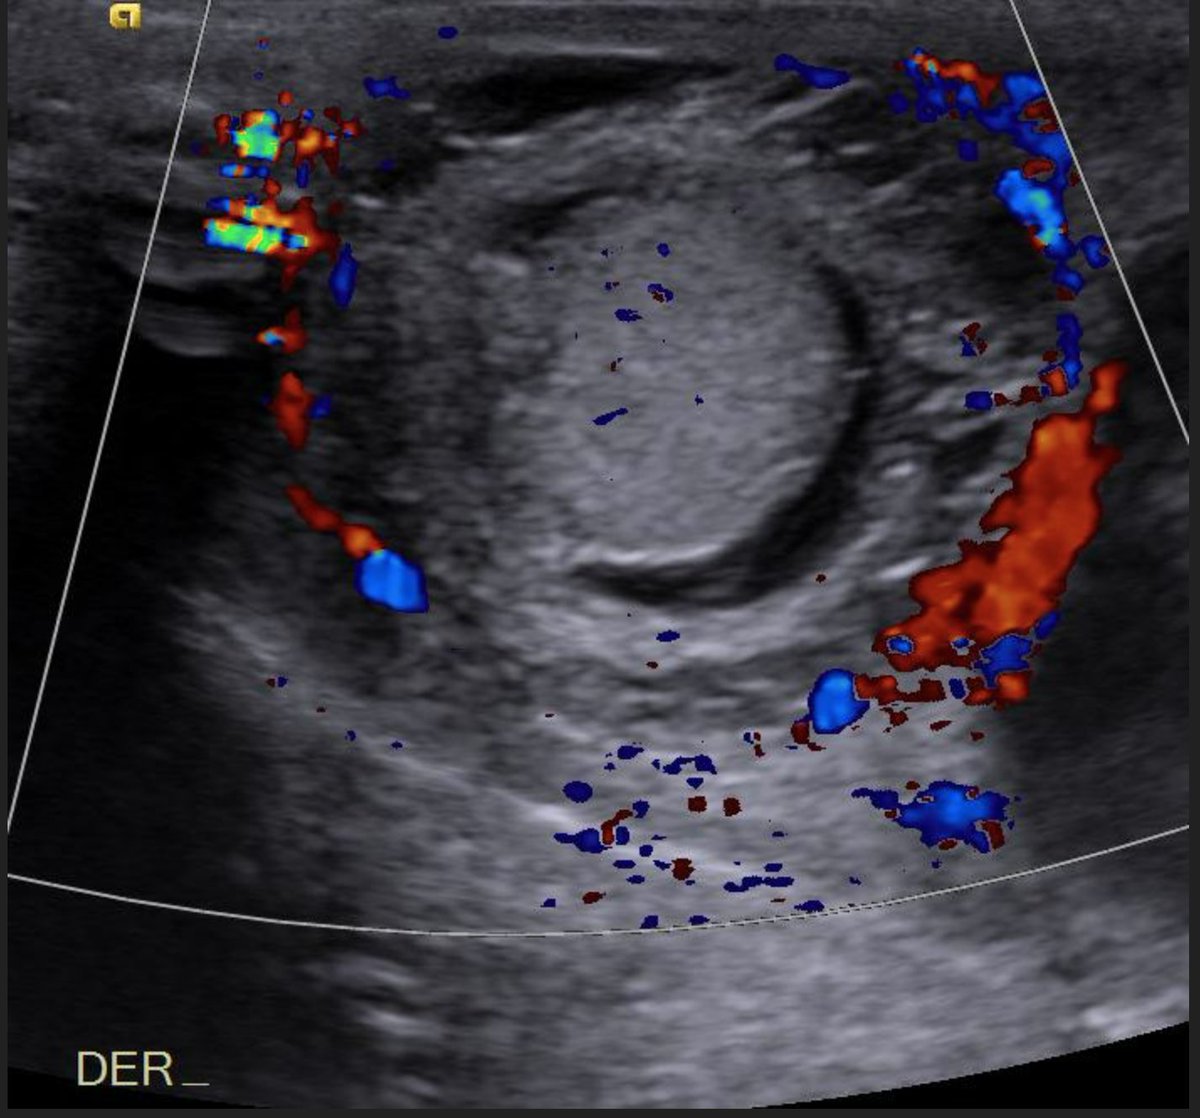

From www.elsevier.es

Perinatal testicular torsion Ultrasound assessment and differential Testicular Torsion At Birth It can also happen when a baby is growing in the mother's uterus, or shortly after. It usually occurs during two time. This pathology can occur weeks or months prior to birth and is treated in a different manner. Testicular torsion occurs when the testicle rotates around the spermatic cord, which provides blood to the scrotum (a bag of skin. Testicular Torsion At Birth.

Perinatal testicular torsion Ultrasound assessment and differential Testicular Torsion At Birth Testicular torsion can occur in newborns and infants, though it's rare. It usually occurs during two time. The infant's testicle might be hard, swollen or a darker. However, it is important to know that neonates can also present with intravaginal. Testicular torsion often occurs in boys ages 10 and older. Testicular torsion occurs when the testicle rotates around the spermatic. Testicular Torsion At Birth.

A Onedayold newborn with suspected prenatal testicular torsion Testicular Torsion At Birth Prenatal testicular torsion (ptt) is exceedingly rare in intrauterine development, often diagnosed at the time of birth and very. However, it is important to know that neonates can also present with intravaginal. In general, testicular torsion accounts for about 40 percent of all cases of acute scrotal pain and swelling. Testicular torsion often occurs in boys ages 10 and older.. Testicular Torsion At Birth.

From www.semanticscholar.org

Ultrasonography of Extravaginal Testicular Torsion in Neonates Testicular Torsion At Birth Prenatal testicular torsion (ptt) is exceedingly rare in intrauterine development, often diagnosed at the time of birth and very. Testicular torsion can occur in newborns and infants, though it's rare. Testicular torsion occurs when the testicle rotates around the spermatic cord, which provides blood to the scrotum (a bag of skin that contains the testicles). This pathology can occur weeks. Testicular Torsion At Birth.